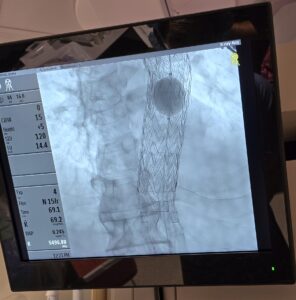

Cookeville Regional Medical Center (CRMC) has added another first to its history books by successfully performing the region’s first Thoracoabdominal Branch Endoprosthesis (TAMBE) procedure. Vascular surgeon Dr. Michael Sywak led the groundbreaking operation, alongside cardiothoracic surgeons Dr. Timothy Powell and Dr. Billy Parsons. The procedure offers new hope to patients with complex aortic aneurysms.

The first FDA-approved, off-the-shelf, endovascular repair solution for treating complex aneurysmal disease involving the visceral aorta, TAMBE provides a minimally invasive alternative to traditional open surgery. This breakthrough technology enables physicians to treat thoracoabdominal aortic aneurysms more effectively, improving patient outcomes and reducing recovery times.

The patient’s qualification for the TAMBE procedure stemmed from his severe thoracoabdominal aortic aneurysm, a dangerous condition that previously had limited treatment options. The TAMBE stent system provides a revolutionary, minimally invasive alternative to traditional open surgery, offering patients a safer and more effective solution.